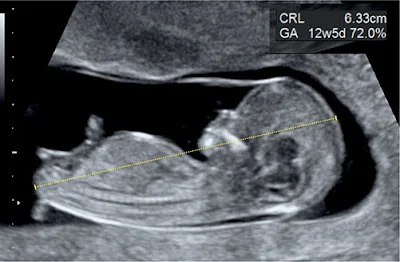

Giải phẫu bình thường hệ thần kinh trung ương thai quý I (Normal CNS anatomy in first trimester)